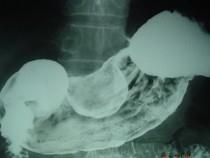

问题 男,52岁,中上腹痛,影像检查如图,最可能的诊断是 ( )

选项 A.慢性肥厚性胃炎 B.胃癌 C.胃溃疡 D.胃平滑肌瘤 E.胃平滑肌肉瘤

答案 D